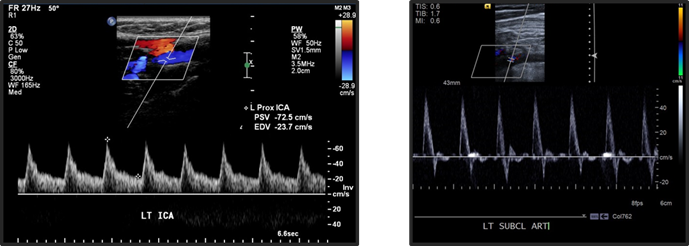

tardus parvus waveform. PROXIMAL stenosis

If shown BILATERAL parvus tardus in the carotids:

aortic stenosis

if you are given a doppler US of the vertebral artery. most likely diagnosis?

subclavian steal.

Resistive Index equation

RI = (PSV - EDV)/PSV

higher diastolic flow is seen in what arteries?

carotid and vertebral artries (lower resistance waveforms –> lower RI)

lower diastolic flow is seen in what vessels?

extremities

lower diastolic flow = higher resistance waveform (higher RI)

due to elastic recoil.

retrograde flow may be seen in early diastole (triphasic flow)